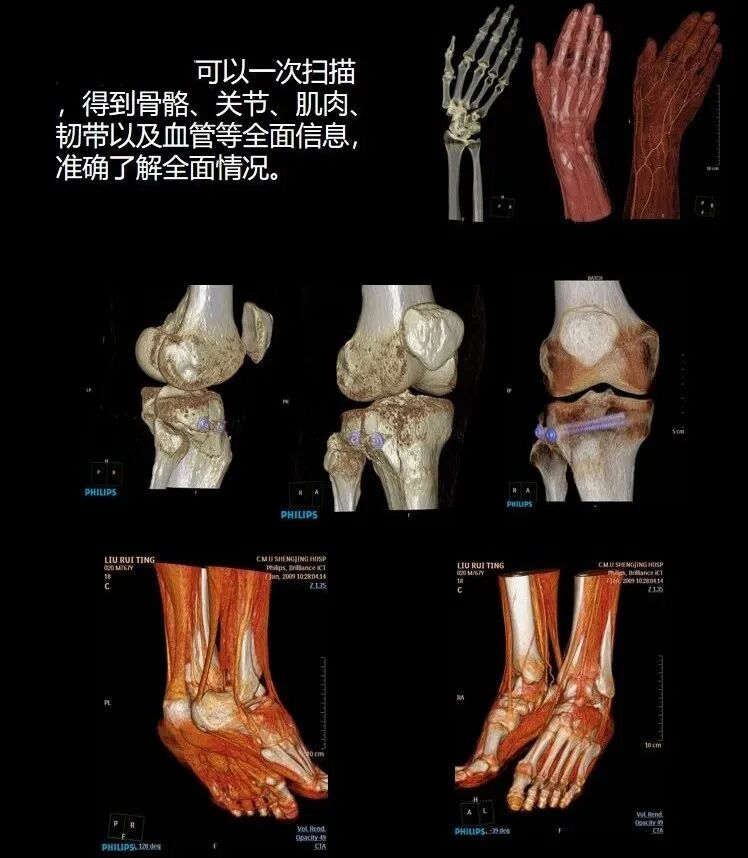

具备快速螺旋扫描能力及大范围门控技术,可实现全身大血管一站式动态观察,精准显示患者各部位信息。可广泛适应于全身各部位各系统的检查,包括头部、颈部、胸部、心脏、腹部、盆腔、脊柱及骨关节、眼耳鼻喉及头面部等部位,尤其是心脑血管疾病、肺部疾病(肺结节筛查等)、肿瘤及骨骼系统疾病等早期诊断、筛查具有重大作用。